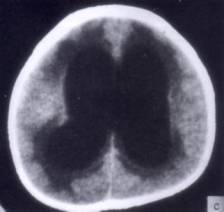

问题 病历摘要:??患者女性,10岁。结核性脑膜炎愈后8月,头痛伴恶心呕吐1周,并渐加重。体检:神清,精神差,反应迟钝,双眼底视神经乳头水肿,双眼外展差,余未见明显异常。 下列关于脑积水的叙述哪些是正确的?

选项 A.按阻塞部位分:梗阻性脑积水和交通性脑积水 B.按脑脊液蓄积部位分:内部性脑积水和外部性脑积水 C.正常颅压脑积水是指脑室扩大,但脑室内压力正常 D.正常颅压脑积水主要症状是步态不稳、记忆力障碍及尿失禁 E.儿童脑积水多为先天性和炎症性病变所致 F.成人脑积水多为颅内肿瘤、蛛网膜下腔出血和外伤所致 G.婴儿脑积水典型症状有Macewen征、日落征等